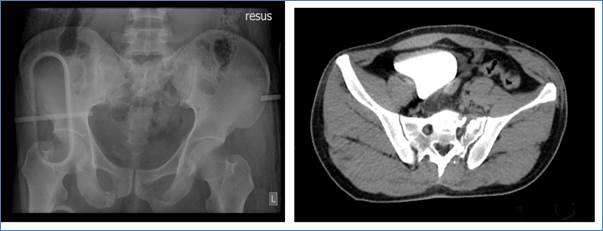

A 31 years old male, Chinese construction worker was involved in a road traffic accident when he was hit by a truck's front wheel while cycling, causing trauma to his left pelvis and left leg. Injuries sustained include comminuted fracture of the left hemi-sacrum, sacral ala involving the left S1-3 foramina (Denis zone 2) along with urethral and penile shaft disruption, fracture of the superior and inferior pubic rami, L5 transverse process fracture, medial collateral ligament damage on left knee. A neurological examination done at the time of admission was intact. Subsequently, he underwent posterior instrumented fusion and stabilization L4 to pelvis and suprapubic catheterization. The rest of the injuries were managed conservatively.

Figure 1. 31-years-old male with polytrauma involving sacral fractures at left S1-3 foramina (Denis zone 2)

Source of Figures 1a,b and Figures 2a, b: Department of Rehabilitation Medicine, Changi General Hospital, 2 Simei street 3 Singapore 529889.